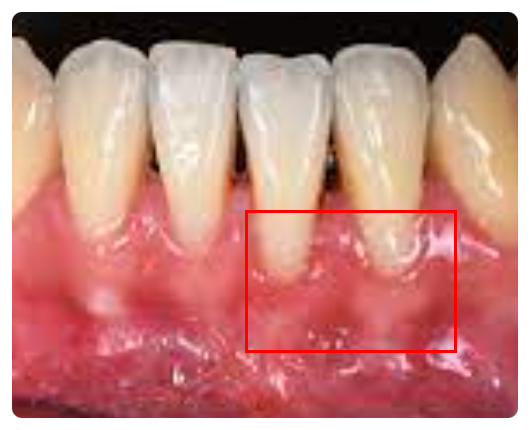

잇몸 내려앉음 영양제 보다 효과 있었던 방법 (원인부터 제대로 알자)

잇몸 내려앉음 영양제 보다 효과 있었던 방법 잇몸 내려앉음 영양제 보다 효과 있었던 방법 (원인부터 제대...